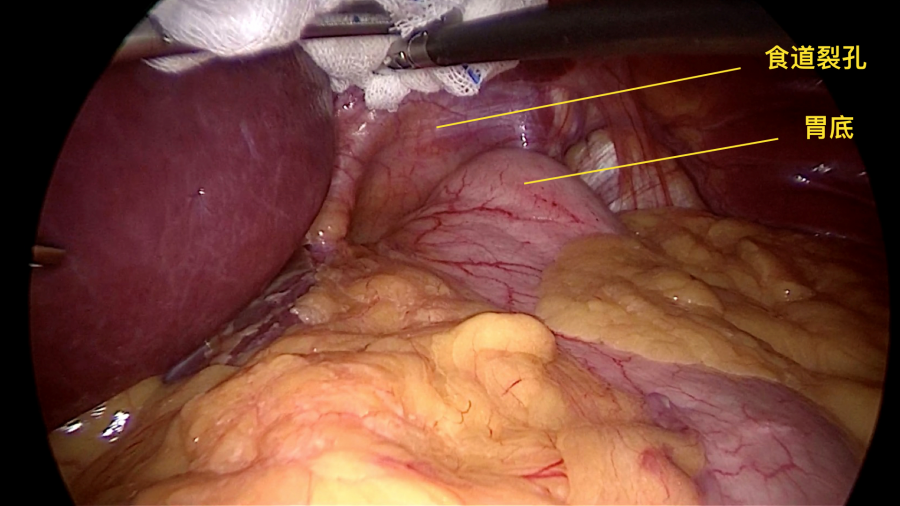

据吴东波博士介绍,人体胸腔和腹腔之间由一层扁平肌肉分隔,叫膈肌,膈肌上有一个裂孔叫食管裂孔,食管穿过膈肌上的食管裂孔进入腹腔与胃相连。正常情况下食管裂孔刚好可容纳食管通过。我们腹腔内压力大于胸腔,当食管裂孔过大,于是压力差会将胃的一小部分"吸入”胸腔内,就称为食管裂孔疝。

图中提示食道裂孔过大

经保守治疗无效,需行手术治疗对于Ⅱ、Ⅲ型疝及症状较重的Ⅰ型食管裂孔疝患者,以及出现食管溃疡、食管狭窄、Barrett食管、食管功能检查证实有较严重的胃食管反流存在、严重出血及吸入性肺炎等应积极采取手术治疗。目前推荐的方法是腹腔镜下食管裂孔疝修补+胃底折叠术。